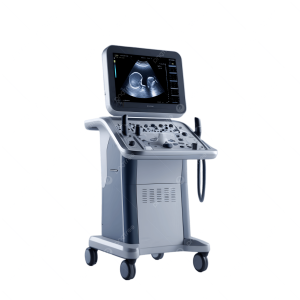

Color Doppler Ultrasound